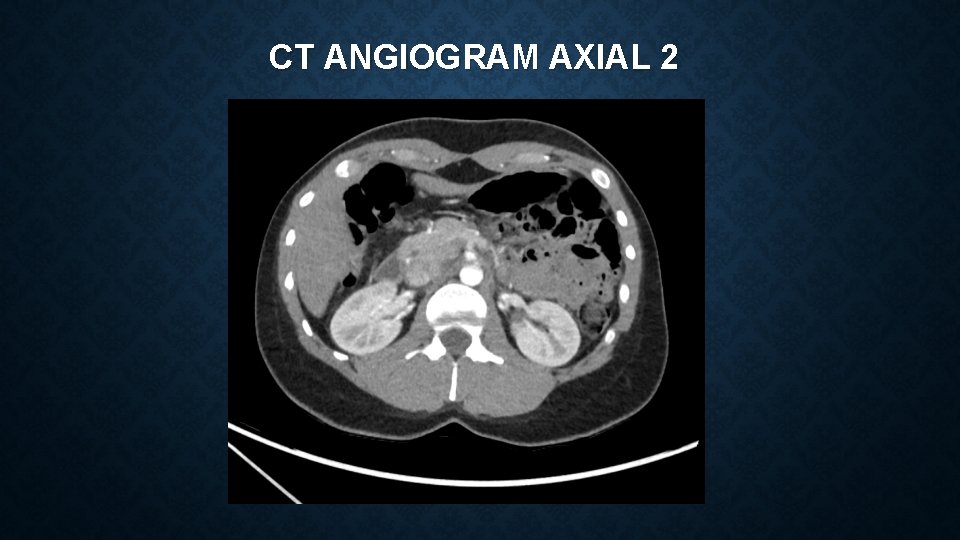

CT ANGIOGRAM AXIAL 2

MEDIAN ARCUATE LIGAMENT SYNDROME Vague constellation of symptoms which can include : • epigastric pain, postprandial pain, chronic non-specific abdominal pain, nausea, vomiting, weight loss Often a diagnosis of exclusion – reliant on clinical features and imaging findings Investigations include – CT angiogram and duplex ultrasonography CT – focal narrowing of coeliac artery with post-stenotic dilatation USS – Peak systolic velocities of >200 cm/s are suggestive of MALS